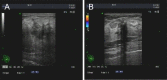

Methods: We present a case that till now is the first reported breast metastasis from rectal cancer pathologically diagnosed as a signet-ring cell carcinoma, and we review the current literature on this rare event. The detailed clinical data, histopathology, management, and follow-up aspects were gathered for analysis.

Results: A total of 15 cases were collected including the current case. Breast metastases from rectal cancer present at an average age of 47.7 years (range, 28 to 69 years) and appear with an average interval of 28.4 months (range, 5 months to 18 years) following primary tumor diagnoses. Of the 15 cases, 8 and 5 are pathologically diagnosed as adenocarcinomas and mucinous adenocarcinomas, respectively. Most cases (11/15) are accompanied by extramammary metastases. About half of the breast metastases (7/15) were to the left. In all cases, the main complaints were palpable mass. The average maximum diameter of the metastatic mass is 2.7 cm (range, 1-11 cm). The majority (8/12) of cases with accessible therapy information exclude the option of local surgery.